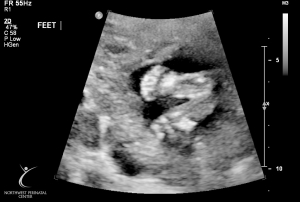

Last Ultrasound